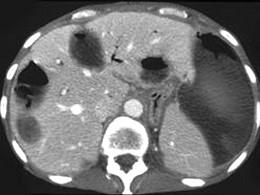

问题 男,67岁,右上腹痛、腹胀,右季肋区叩击痛,体温39℃,CT检查如图,最可能的诊断是 ( )

选项 A、肝转移癌 B、肝淋巴管瘤 C、多发性肝脓肿 D、肝包膜下出血伴囊变 E、多发性肝囊肿

答案 C